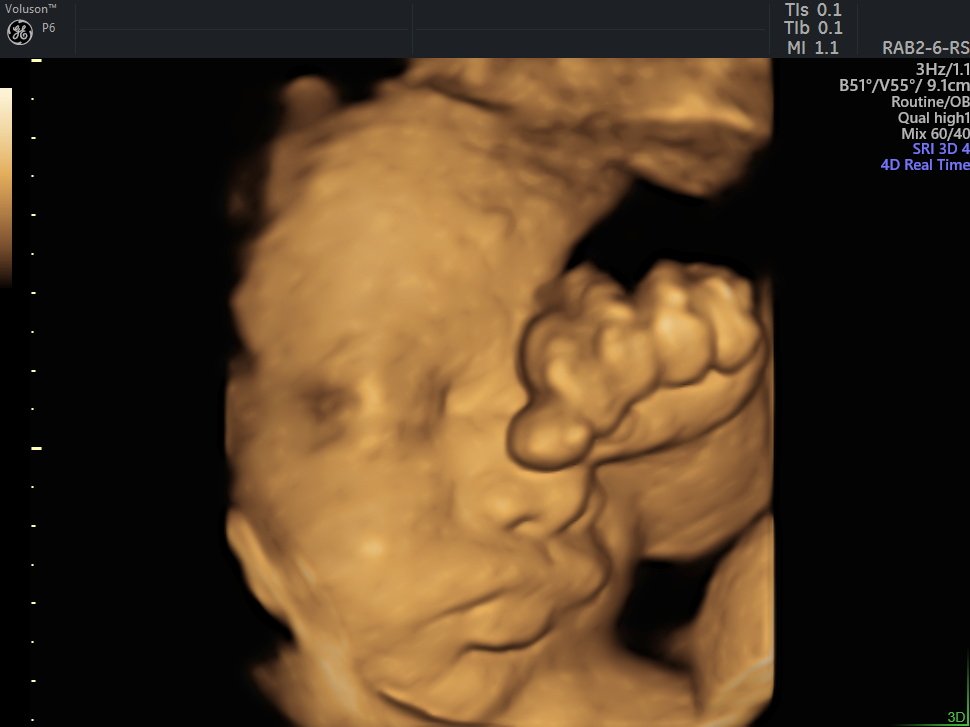

4 Boyutlu (Renkli) Ultrason ve Doppler Ultrasonografi

4 D Ultrasonografi